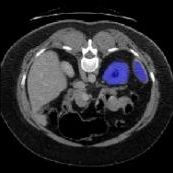

Figure 3 illustrates the specific segmentation results on the SABS dataset under Setting 1. Our model demonstrates higher accuracy in segmentation and effectively reduces unnecessary segmentation. Even under Setting 2, where the test class is entirely invisible to the model, our model performs well, as depicted in Figure 4. Given that SABS is a multi-organ dataset with many organs of small size, precise segmentation proves challenging. However, our model excels, particularly in the scenario of completely invisible classes, which closely resembles real-world conditions. Figure 4 highlights our model’s ability to accurately segment very small target organs, such as the right kidney. In contrast, the ADNet method fails to produce effective segmentation predictions, and other methods exhibit varying degrees of over-segmentation. On the CMR dataset, as shown in Table 2, our model generally outperforms others.

Figure 5 provides a visual representation of our model’s segmentation, indicating its superior accuracy, particularly in the right ventricle (RV) organ. While other methods display complete segmentation, our segmentation aligns more closely with the real mask.